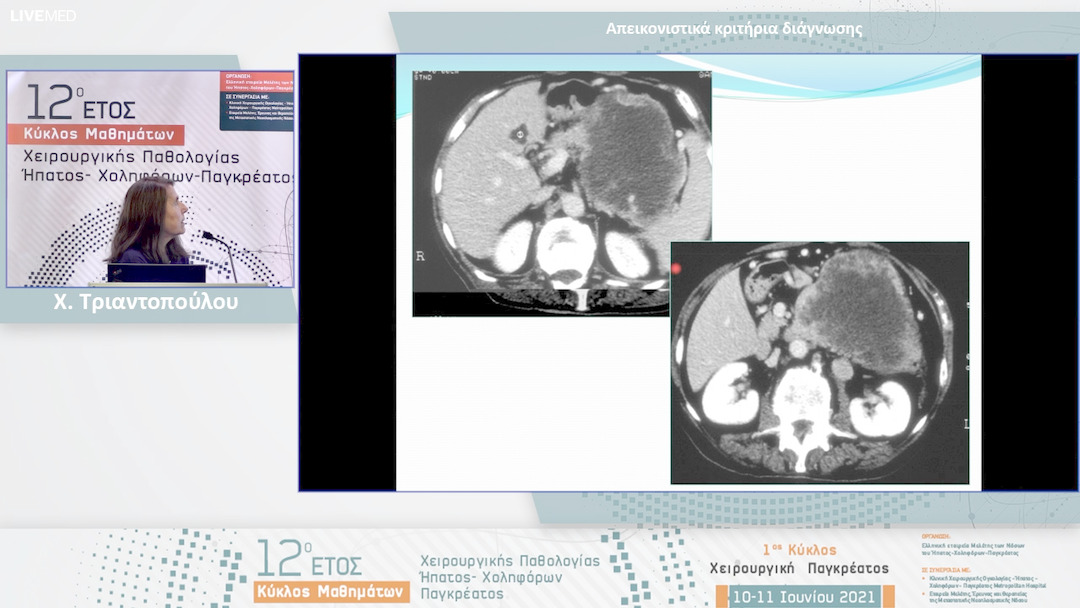

06 Χ. Τριαντοπούλου - Απεικονιστικά κριτήρια διάγνωσης